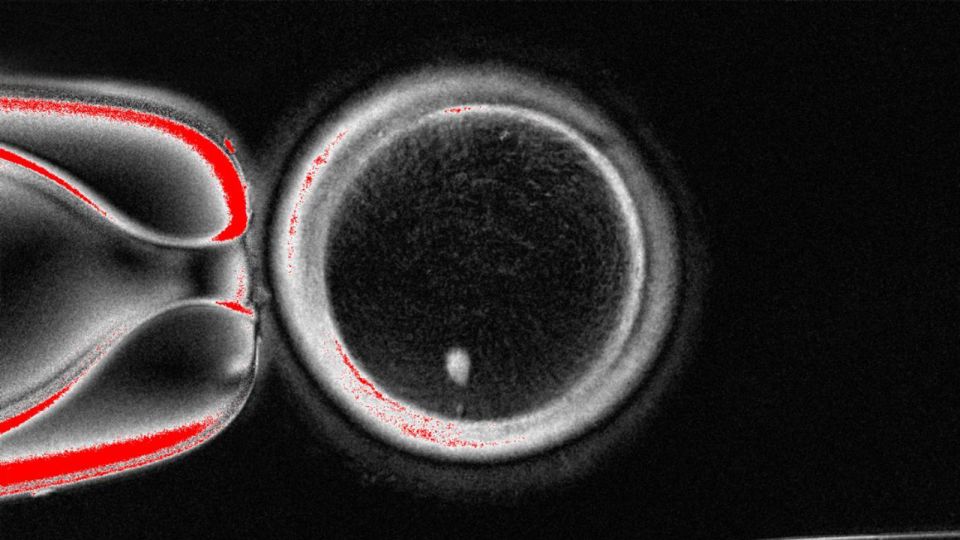

تضمنت دراسة إثبات المفهوم ، التي نشرت يوم الثلاثاء في مجلة Nature Communications ، أخذ النواة ، وهي جزء من الخلية التي تحتوي على معظم معلوماتها الوراثية ، من خلية الجلد البشرية العادية وزراعةها في بيضة مانحة جردت من نواةها. أنتج الباحثون 82 البويضات البشرية الوظيفية ، أو خلايا البيض غير الناضجة ، والتي خضعت بعد ذلك للإخصاب في المختبر.

ومع ذلك ، استمر أقل من 9 ٪ من البيض الذي تم إنشاؤه خلال الدراسة للوصول إلى مرحلة الكيسة الأريمية من تطور الجنين ، أي ما يعادل خمسة أو ستة أيام ما بعد الاستقرار. هذا هو الوقت الذي يتم فيه نقل الأجنة عادة إلى الرحم أثناء علاج الإخصاب في المختبر.